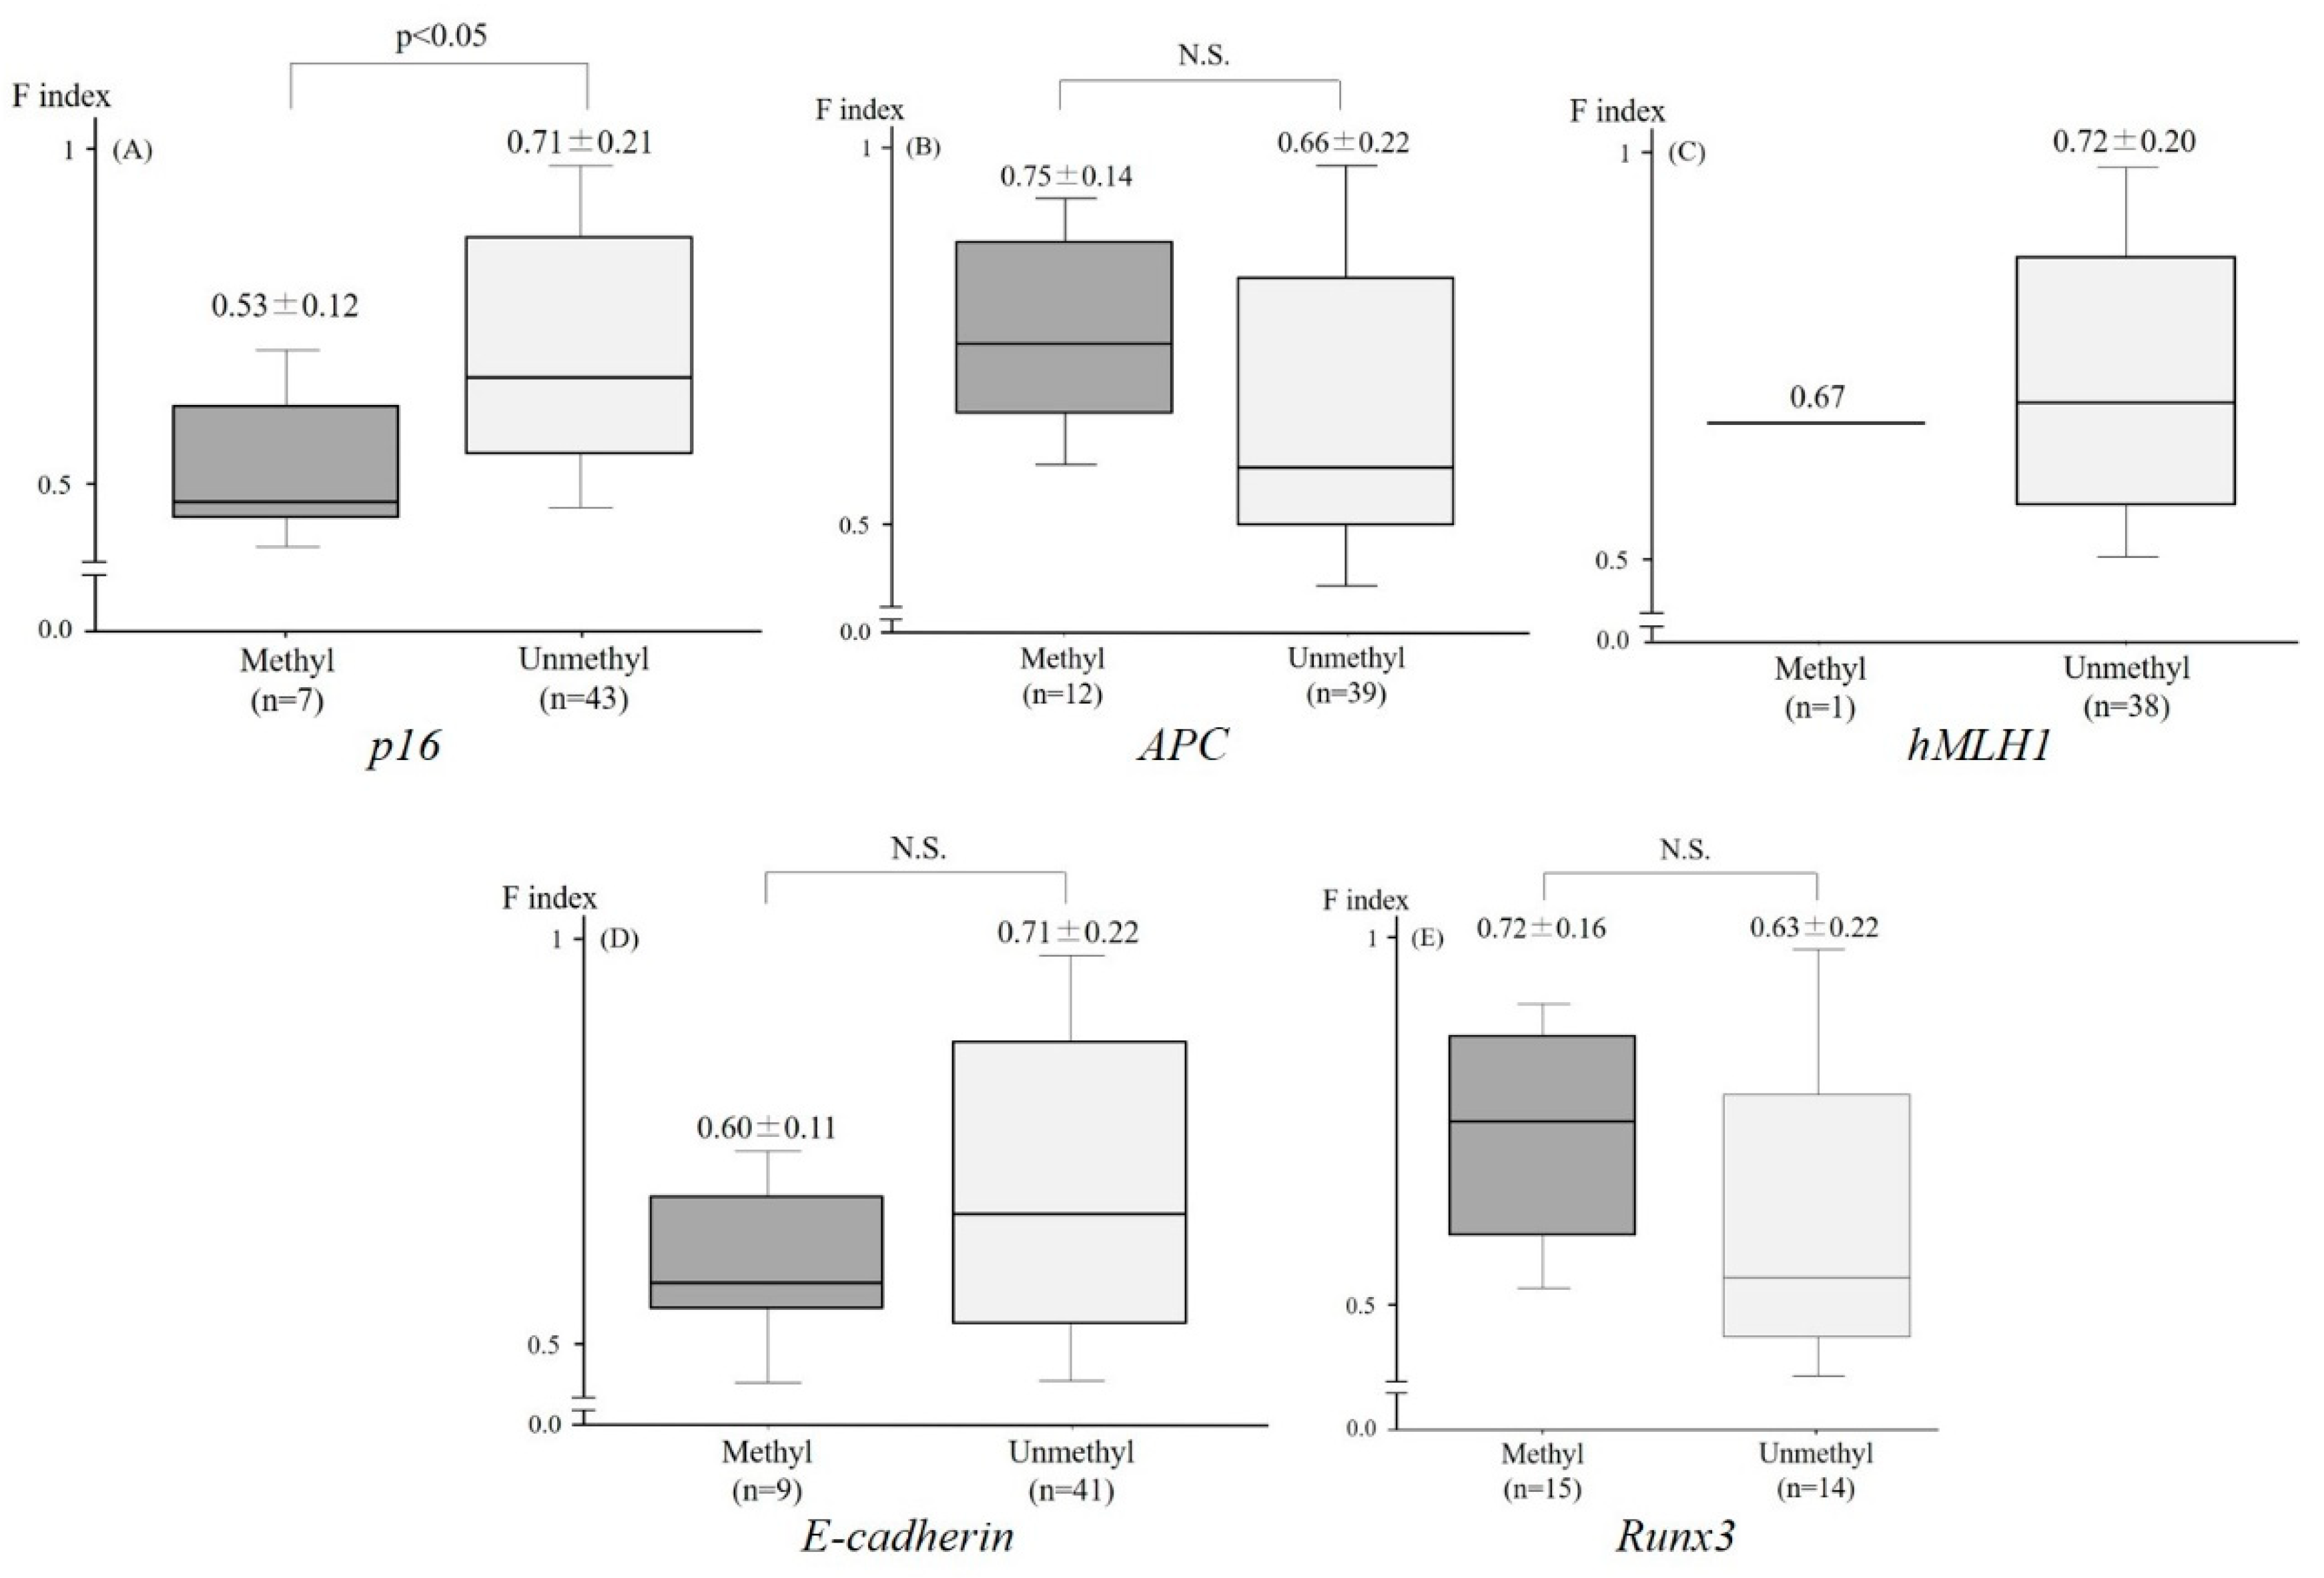

2.3. Relationship between the F index and the Aberrant Methylation of Tumor-Related Genes